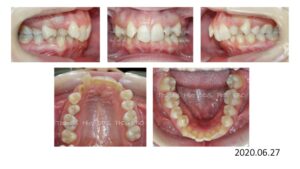

8歳の時、I市の歯科医院で、顎が狭くて歯が入りきらない、顎を拡げなければいけないといわれ、治療を開始したそうですが、6年経っても治療が終わらないどころか、写真のように全く噛み合っていないために、14歳の時にセカンドオピニオンで ひろ矯正歯科に来られました。

臼歯関係は、右が 4㎜ II級。左が 7㎜ II級で、7番しか咬合しておらず、著しい開咬を呈していました。

これは、拡大を始める前の写真ですが、口腔内写真を見る限り、拡大する必要はないです。